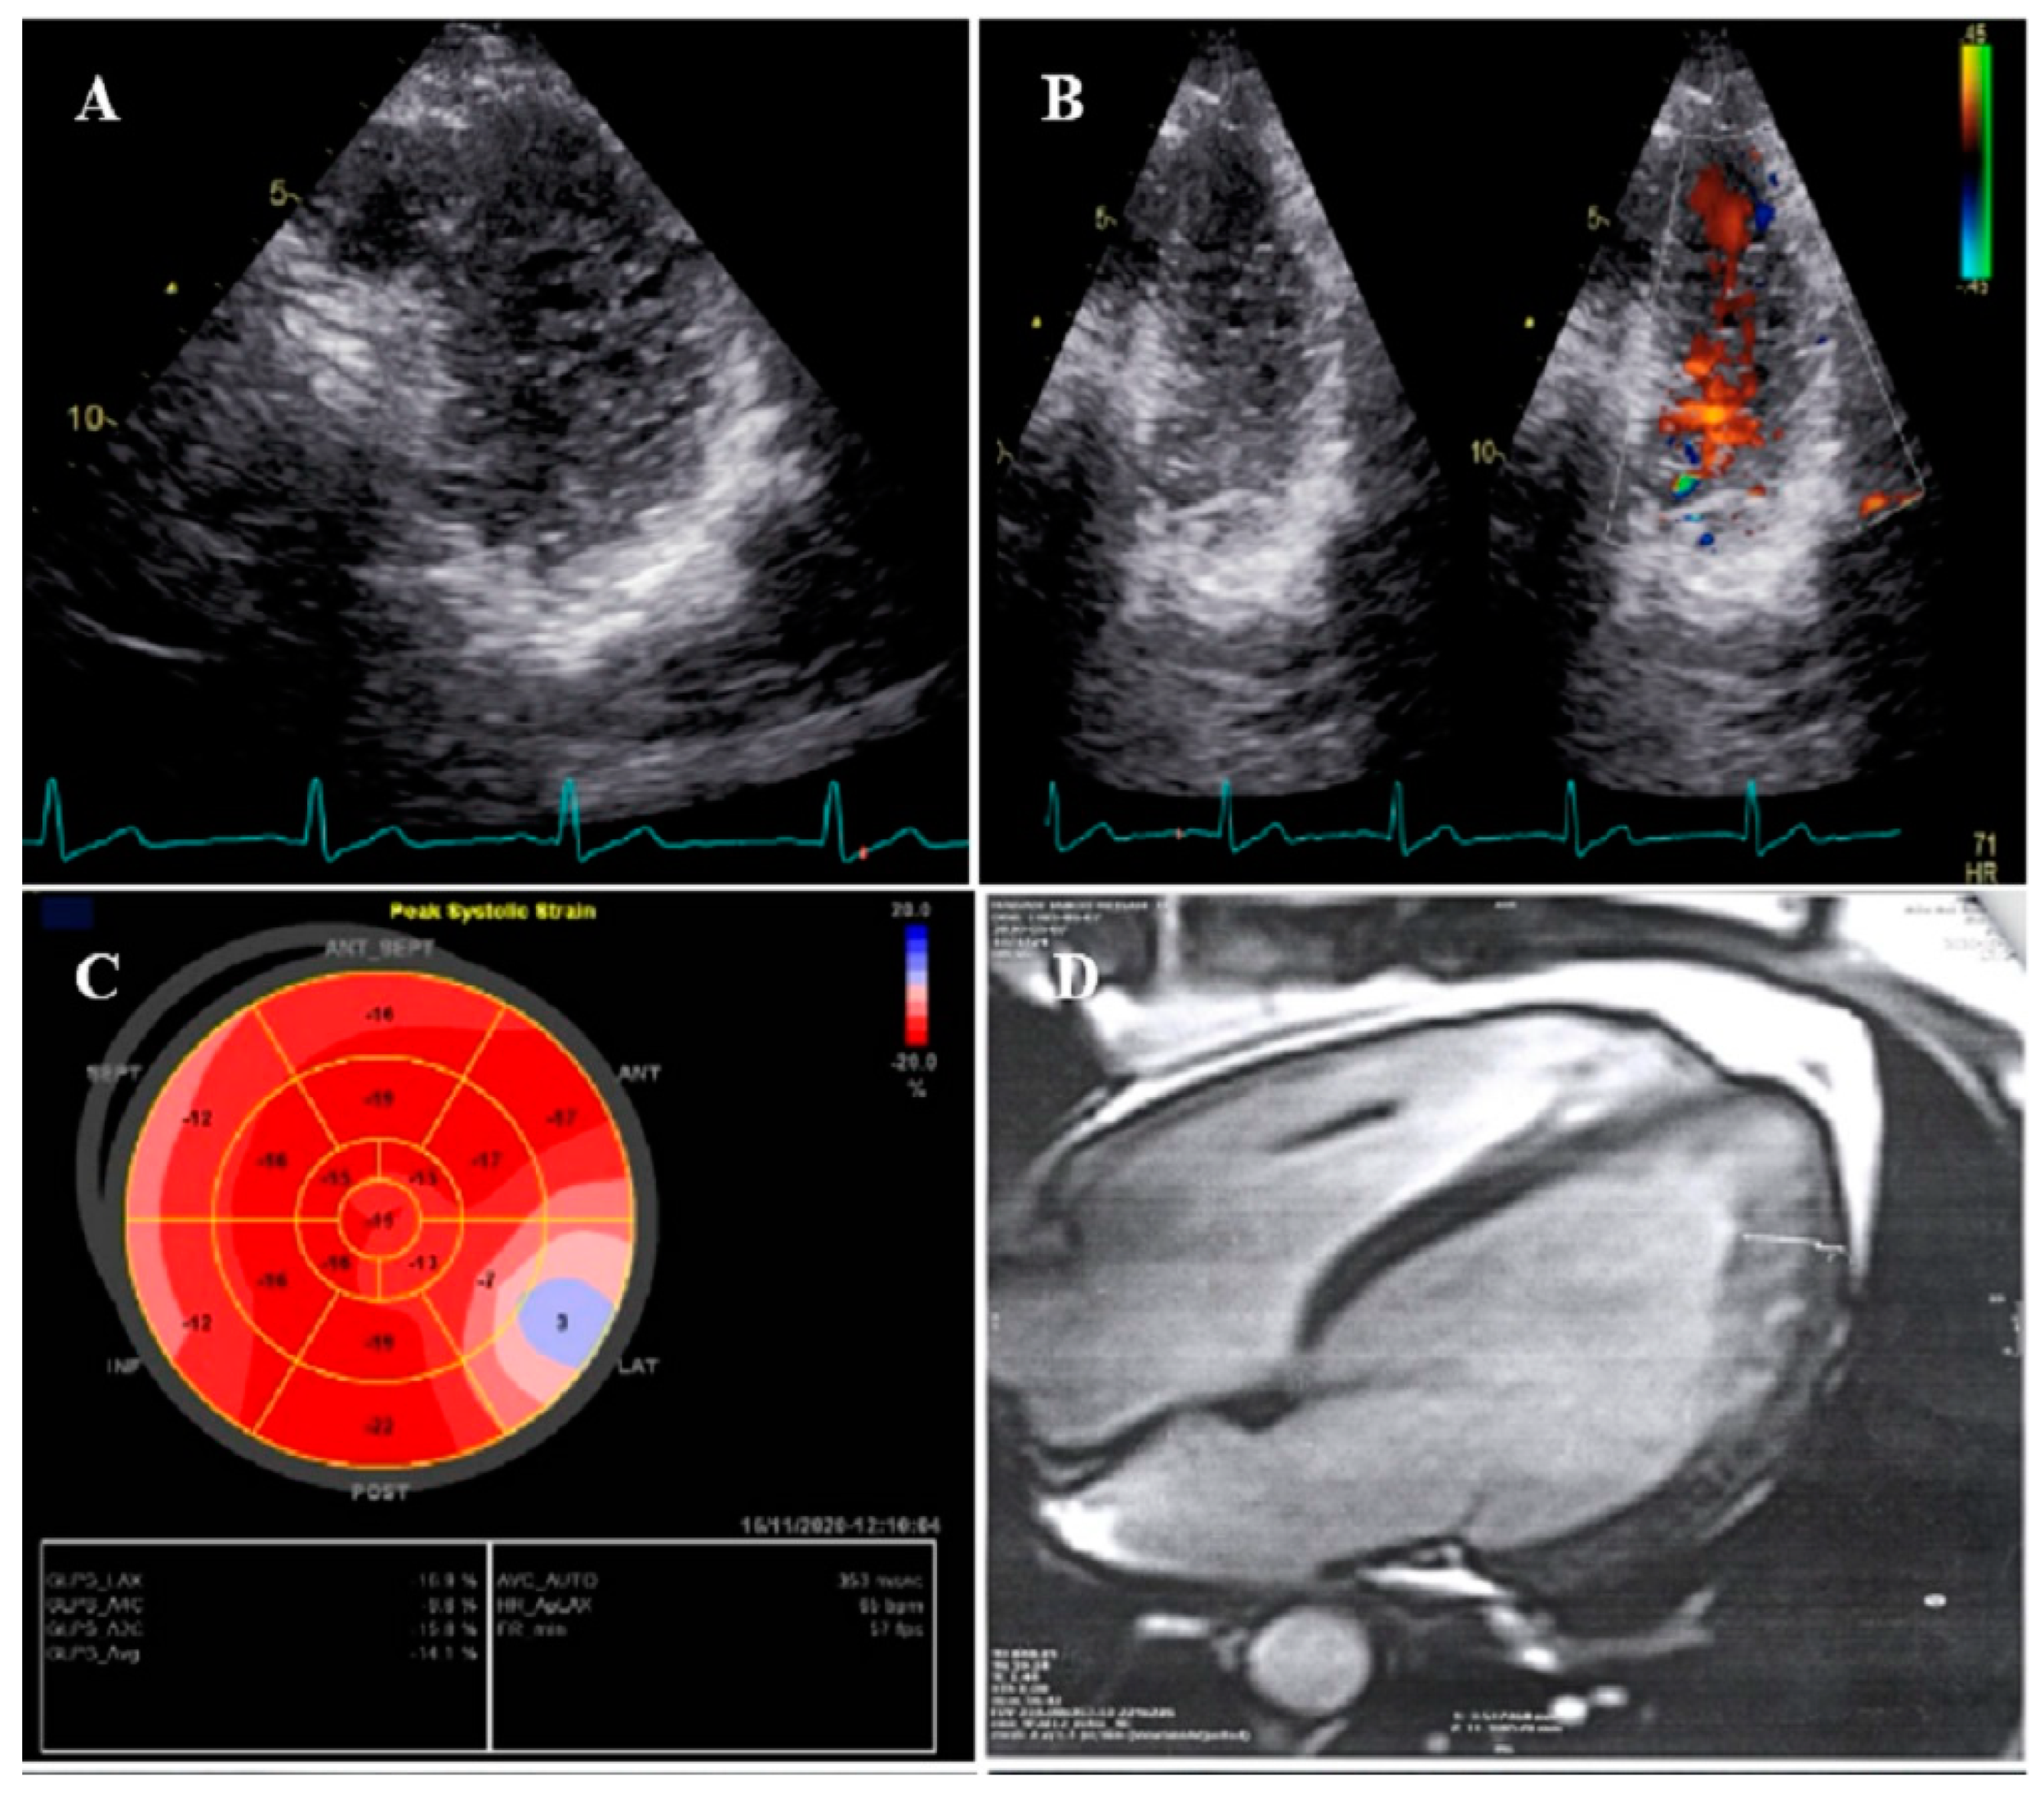

2.1. Case #1. NCLV and Coarctation of the Aorta

| 1 | M | 47 | Easy fatigability and mild hypertension since two years ago | HTN | NCLV, reduced LVEF (45%) | Coarctation of aorta | + | + | Carvedilol 6.25 mg TID plus spironolactone 25 mg daily | Good conditions |